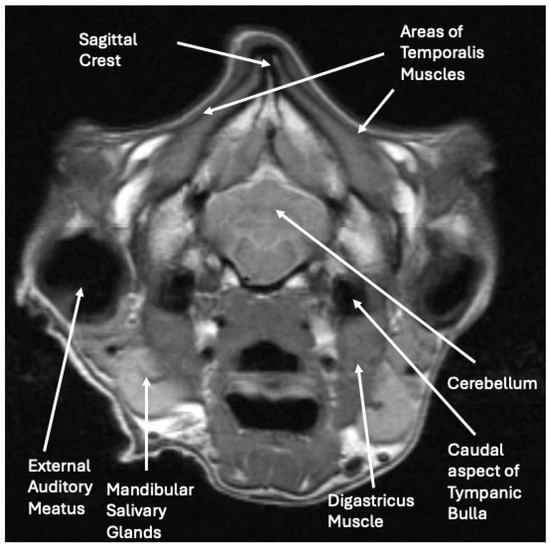

2.2. Diagnostic Imaging Findings and Interpretation

The radiographs and abdominal ultrasound performed at the previous referral hospital revealed no significant systemic disease findings. The MRI images indicated severe atrophy of the temporal, masseter, and pterygoid muscles bilaterally with multifocal ring enhancement and focal mineralization or hemorrhage of the right temporal muscle (Figure 3). Muscle denervation, necrosis, and fibrosis secondary to the reported traumatic event with suspected vascular and innervation compromise were considered the most likely cause for the changes noted on the MRI. The EMG activity of the masticatory muscles bilaterally was silent, suggesting diffuse fibrosis and a loss of function. The pre-operative radiographs demonstrated normal skeletal structures.

Figure 3.

Cross-sectional MRI image at the level of the caudal cerebellum, internal auditory canal, and middle ear, demonstrating severe atrophy of the temporalis muscles.